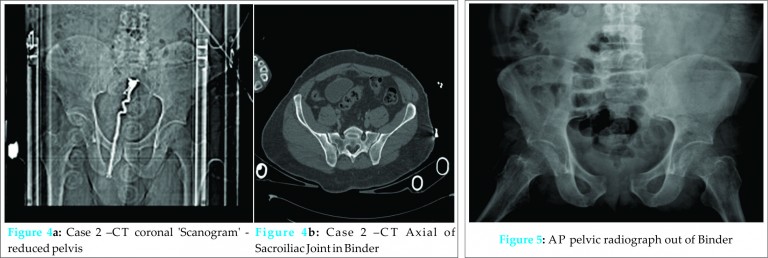

A trauma CT was performed, which showed multiple vertebral fractures at C1, T4 and T6. The worst was at the level of T6 with extensive damage to the pedicles and intervertebral discs. The CT was reported as no solid organ damage, vascular damage nor pelvic bony injury (Figs. 4a and 4b). His pelvic binder was removed, though he remained triple immobilised due to his spinal injury. When he was stable he was admitted to the high dependency neurosurgical ward and a MRI showed narrowing of the vertebral canal at T5 and T6 without cord compression. The cord was swollen and oedematous at both levels in keeping with an acute cord injury; his spinal fractures were managed non-operatively. He was transferred to a spinal rehabilitation unit for on-going management due to his neurological deficit. Fig. 5 – Case 2 – AP pelvic radiograph out of Binder At a 3 month spinal follow up appointment, a plain radiograph of his spine was repeated which showed widening of the pubic symphysis. Plain pelvic radiography showed this widening with a widened left sacroiliac joint (Fig. 5); injuries that were missed on his initial assessments.

A 54-year-old male, was a motorcyclist versus car at a combined speed of 60mph. He was managed using the ATLS protocols and was transferred directly to the regional trauma centre. His assessments demonstrated superficial facial bruising with significant bruising and tenderness over the right clavicle with demonstrable crepitus. He also had blood around the external urethral meatus associated with a scrotal haematoma, tenderness over T6 with an obvious bony deformity and associated distal complete neurological deficit.